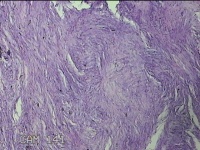

右拇指远端结节

性别

男

年龄

37岁

临床诊断

皮脂腺囊肿

一般病史

发现右拇指远端结节2年余。

标本名称

大体所见

灰白粉红色组织1.8x1.2x00.8cm一个,表面带梭形皮肤1.3x0.7cm,皮下见结节1.2x0.8cm一个,切开结节呈实性,切面灰白粉红色,质中。

图4